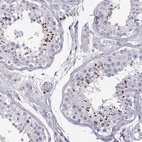

Immunohistochemistry analysis in human testis and endometrium tissues using Anti-ZBTB32 antibody. Corresponding ZBTB32 RNA-seq data are presented for the same tissues.